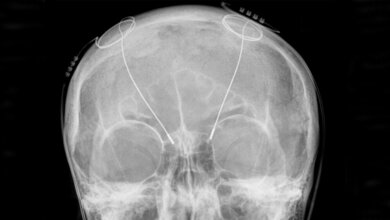

Die acht Probanden litten zwischen drei und elf Jahre durchgehend an einer schwersten Depression, bei der weder medikamentöse oder psychotherapeutische Behandlungen noch Stimulationsverfahren wie die Elektrokrampftherapie Besserung brachten. Die Ärzte implantierten hauchdünne Elektroden und stimulierten einen Hirnbereich, der an der Wahrnehmung von Freude beteiligt und damit auch für Motivation und Lebensqualität von Bedeutung ist. Die Wirkung der Therapie bewerteten die Ärzte monatlich mit Hilfe der etablierten Montgomery-Asberg Rating Scale (MARDS). Bereits im ersten Monat fiel der MARDS-Wert im Durchschnitt von 30 Punkten auf 12 Punkte und sank bis zum Ende der Studie sogar noch weiter leicht ab. Den MARDS-Wert von 10 Punkten, ab dem eine Depression diagnostiziert wird, unterschritten vier Personen.

Manche Patienten litten kurzzeitig unter verschwommenem Sehen oder unter Doppelbildern. „Die Nebeneffekte konnten wir durch eine verminderte Stimulationsstärke beheben, ohne dass der antidepressive Effekt der Therapie nachgelassen hätte“, sagt Prof. Dr. Volker A. Coenen, Leiter der Abteilung Stereotaktische und Funktionelle Neurochirurgie an der Klinik für Neurochirurgie des Universitätsklinikums Freiburg. Bei keinem Patienten waren Persönlichkeitsveränderungen, Denkstörungen oder andere Nebenwirkungen zu beobachten.